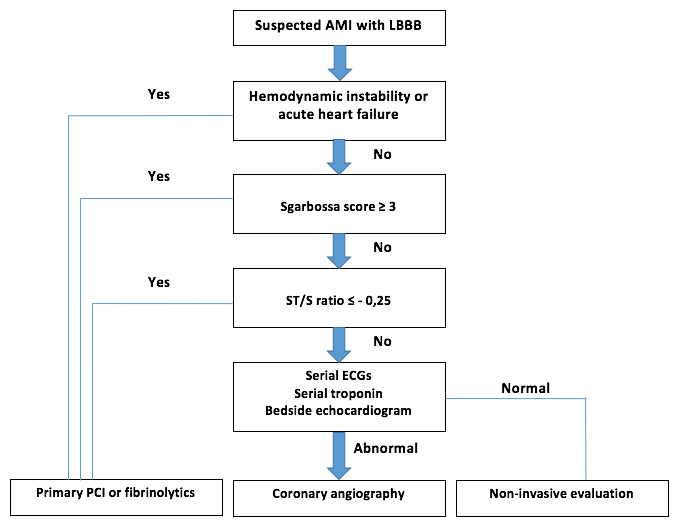

propagierter Algorithmus aus (2). AMI= acute myocardial infarction, LBBB = left bundle branch block